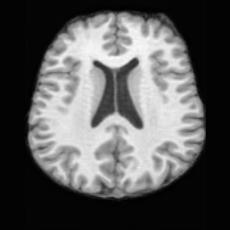

(a)PathologicalInput ImageSynthSR [18]Brain-ID [28]UNA [30]USBHealthyGround TruthRefer to captionRefer to captionRefer to captionRefer to captionRefer to captionRefer to captionRefer to captionRefer to captionRefer to captionRefer to captionRefer to captionRefer to captionRefer to captionRefer to captionRefer to captionRefer to captionRefer to captionRefer to captionRefer to captionRefer to captionRefer to captionRefer to captionRefer to captionRefer to caption(b)HealthyInput ImageConditionalLesion MaskUNA [30]USBRefer to captionRefer to captionRefer to captionRefer to captionRefer to captionRefer to captionRefer to captionRefer to captionRefer to captionRefer to captionRefer to captionRefer to captionRefer to captionRefer to captionRefer to captionRefer to caption

Figure 5: Comparison of bidirectional brain editing. (a) pathology-to-healthy, the circles and arrows highlight lesion regions and unsuccessful reconstructions; (b) healthy-to-pathology. Note that SynthSR and Brain-ID cannot perform healthy-to-pathology editing.

Pathology-to-Healthy Editing. Fig. 5 (a) presents comparison results on four input brain images with lesions of varying sizes, shapes, and densities. All competing models, although specialized for healthy brain image synthesis, struggle to reconstruct pathological regions, especially near lesion boundaries. In contrast, USB accurately reconstructs the corresponding healthy brain, even in challenging cases with large, high-density lesions where normal brain structures are almost completely obscured (last row). Tab. 2 provides a quantitative comparison for pathology-to-healthy editing, where USB achieves the best performance across all three datasets, demonstrating the effectiveness of its unified framework in reconstructing healthy brains from pathological inputs. Additional results are in Suppl. B.